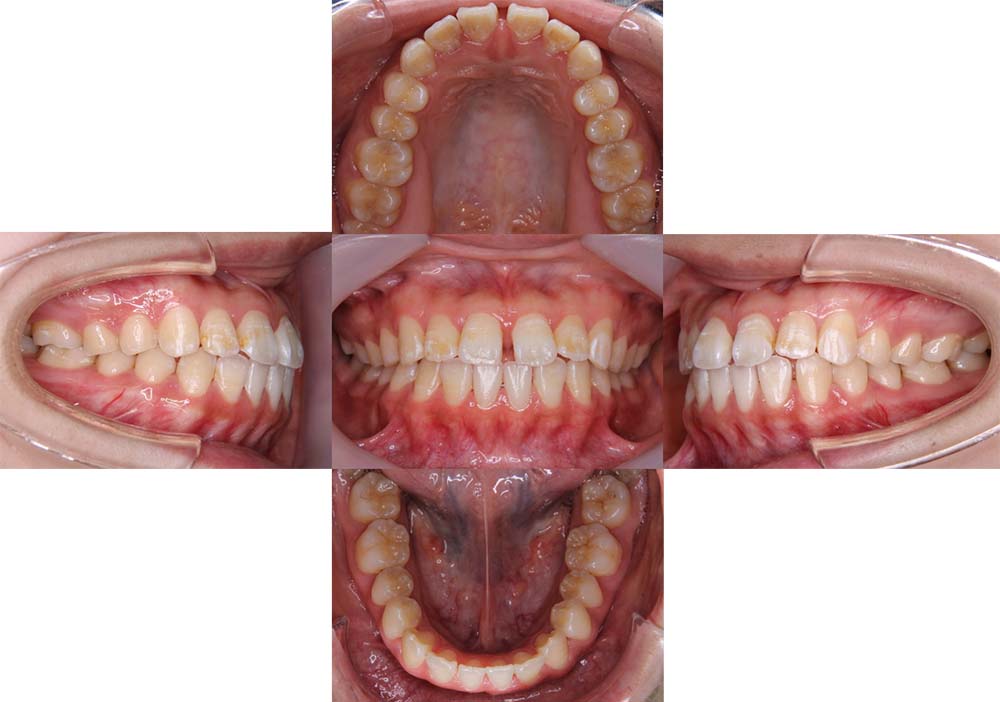

症例01

| 主訴 | 歯並びがガタガタしている。 |

| 診断名あるいは主な症状 | 叢生 |

| 年齢/性別 | 22歳・男性 |

| 矯正ステージ | 大人の矯正治療 |

| 治療方法 | ワイヤー矯正 |

| 抜歯部位/抜歯有無 | 非抜歯 |

| 治療内容 | 上顎大臼歯の遠心移動により前歯のガタガタを排列スペースを獲得し全顎的な排列を行った。 |

| 費用 | 85万円程度(2025.10時点の料金となります。) ※矯正基本料金、審美ブラケットを含む |

| 治療期間 | 2年4ヶ月 |

| 主なリスク・副作用 | 痛み、歯根吸収、歯肉退縮、虫歯、後戻り |